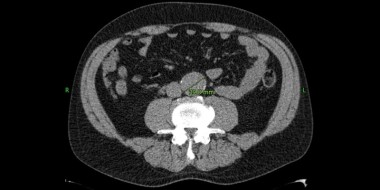

• Een snelgroeiend aneurysma van de buikaorta

Soms wordt op een echo of CT van de buik een aneurysma aortae abdominalis (AAA) ontdekt. Vaak gebeurt dat in een ziekenhuis. De radioloog vermeldt die toevalsbevinding meestal wel in de brief aan de huisarts, maar als het AAA ‘klein’ is, wordt meestal niet vermeld dat follow-up geïndiceerd is. Die controle kan echter van levensbelang zijn.